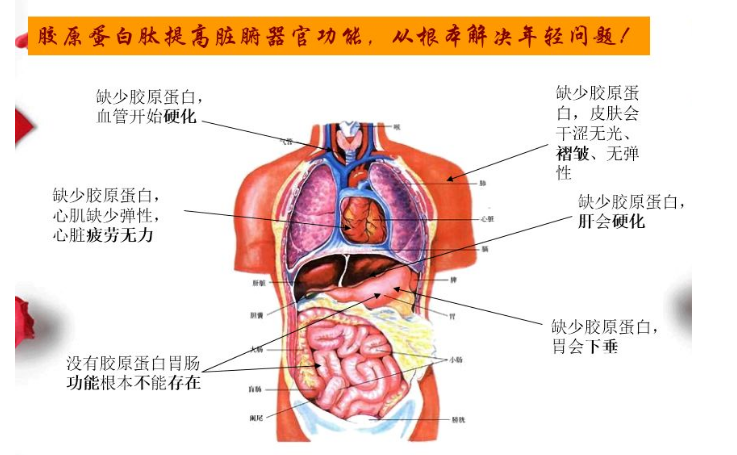

娇颜胶原蛋白